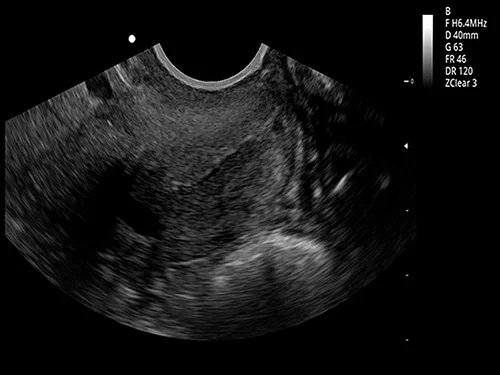

EVORAY USS 20 — стационарная ультразвуковая диагностическая система, разработанная и произведённая компанией Evoray как базовая модель линейки USS для повседневной клинической работы. Аппарат предназначен для оснащения кабинетов ультразвуковой диагностики общего профиля и обеспечивает стабильную визуализацию, точные измерения и удобный рабочий процесс при рутинных исследованиях.

Конвексный датчик 3C5PD

• Рабочая полоса частот: 1,0–7,5 МГц

• Количество элементов: 128

• Радиус кривизны: 50 мм

• Применение: абдоминальные исследования (органы брюшной полости и забрюшинного пространства), общая диагностика.

EVORAY USS 20 применяется для:

1. Исследование органов брюшной полости и забрюшинного пространства (печень, почки, селезенка, желудок и кишечник, поджелудочная железа, мочевой пузырь, желчный пузырь и т.д.)